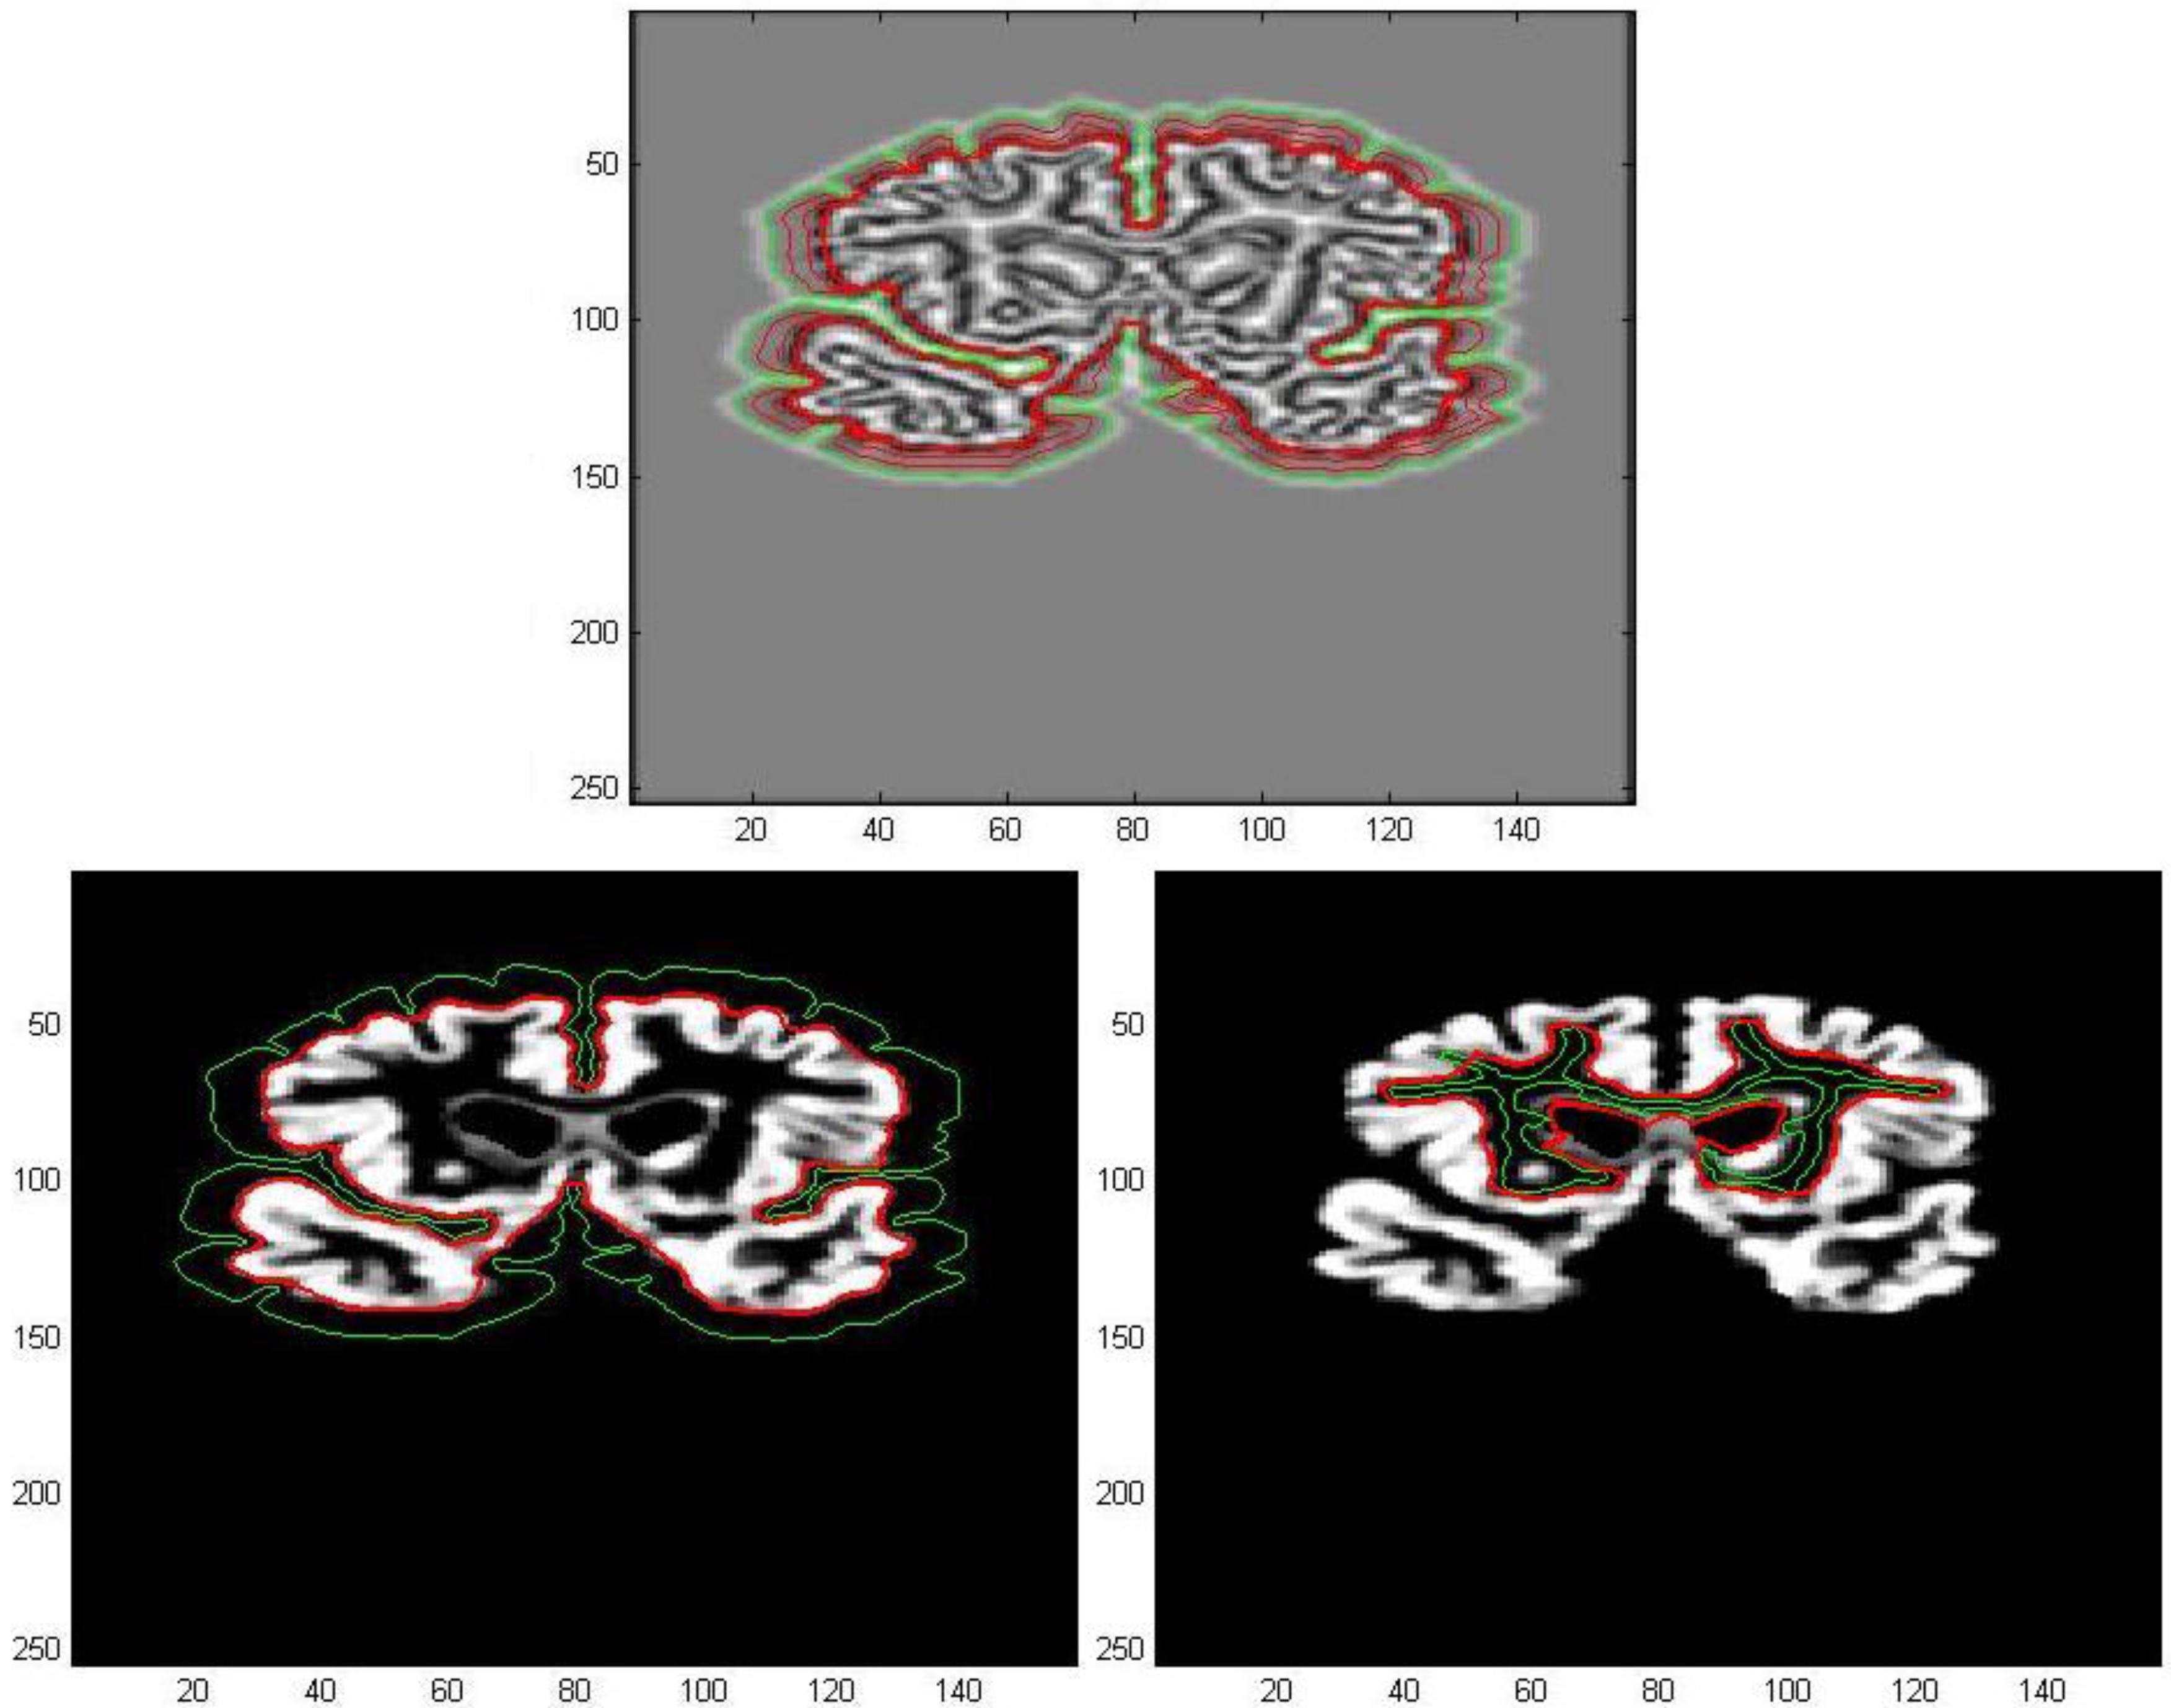

The first processed GM image (Figure 11) refers to a subject of the control group (see the first image of Figure 12). The force field has been evaluated from Equation (9) after eight iterations, the overlapping green curves represent initial contours that are automatically selected from the contour map of divergence. In Figure 13 and Figure 14 we have treated GM images derived from two patients affected by Alzheimer’s disease and they refer respectively to the second and third images which are shown in Figure 12. Once edges are detected, we produce a boundary representation of gray matter that can be used for an automatic analysis of shapes from the geometrical, metrical or morphological point of view.

Figure 13. Edge extraction with AVF force field after 8 iterations.

Algorithms 05 00636 g013